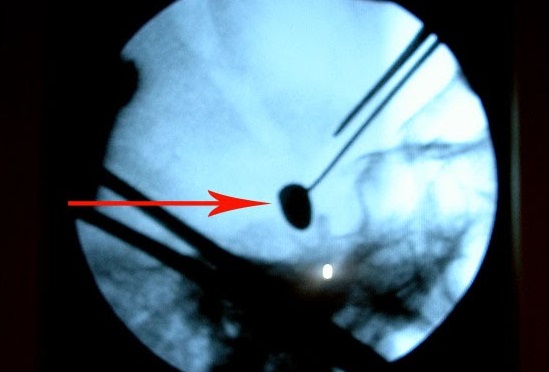

„A fost foarte greu de localizat glonțul. Nu exista încă neuronavigația. Am efectuat operația prin radiografia intraoperatorie. Cu greu am găsit glonțul, căci era amplasat în creier la o adâncime foarte mare. Succesul meu ca neurochirurg a fost nu doar extragerea glontelui, dar și faptul că pacientul după operație putea sta în picioare, putea sta așezat, a început să perceapă unele comenzi de la cei apropiați, iar când l-am externat, mi-a dat mâna și și-a luat rămas bun. Bucuria mea a fost că tânărul a venit la Chișinău fiind adus pe targă, dar a plecat stând așezat în mașină”, a mărturisit directorul INN, Grigore Zapuhlîh.

Starea după înlăturarea glonțului endocranian prin abord supraorbital stânga era satisfăcătoare, în ameliorare cu prezența mișcărilor spontane în toate extremitățile. Glonțul a fost extras cu succes fără apariția complicațiilor neurologice, în două săptămâni, pacientul fiind externat.